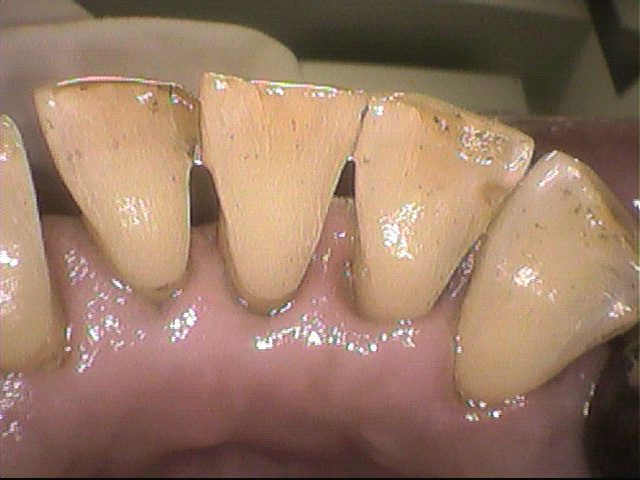

クリーニング後

特に汚れが目立っていた下の前歯を中心に、できる限り除去しました。

とてもスッキリしました!と喜ばれていました。